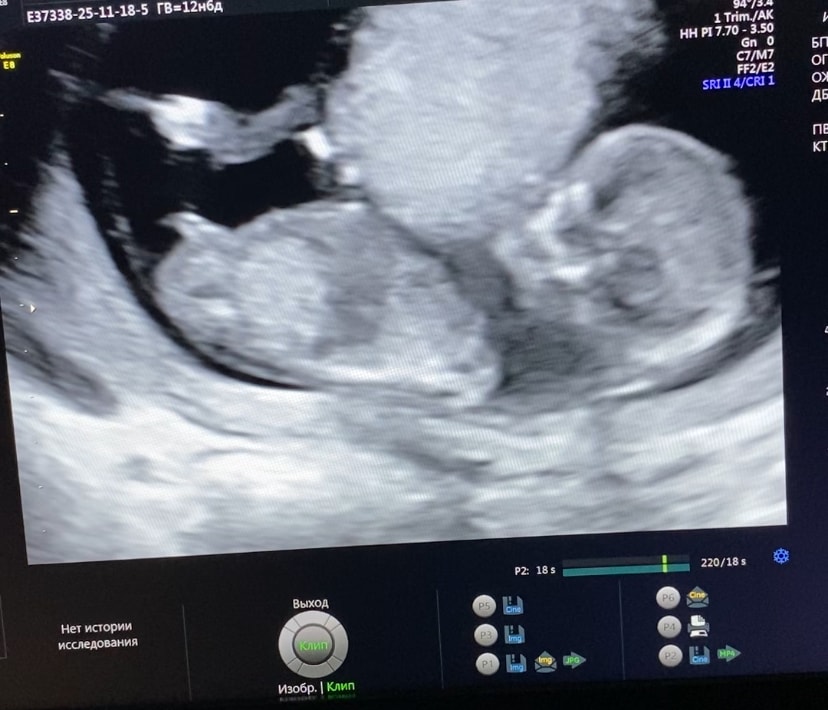

Ну если это половой бугорок то скорее всего девочка.

Нам на узи говорили что обычно если этот бугорок направлен вниз, то девочка, а если вверх, то мальчик))) но бывает всякое :)

Инга, я так на 3д картине узи увидела что то торчащее😂 сравнивала потом снимки узи мальчика и девочки, еще определяют по жопке как то 🤣 вообщем в сравнении мальчика и девочки, у парня достоинство должно смотреть вверх 😁

Галчонок, ага я аж картинку развернула чтобы позвоночник ровнее на прямой линии был)) и тоже аж сомневаюсь что это бугорок поэтому так неуверенно и написала))